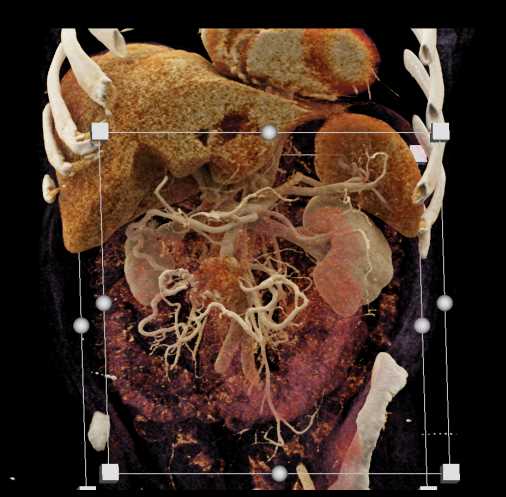

Carcinoid Tumor with Desmoplastic Reaction